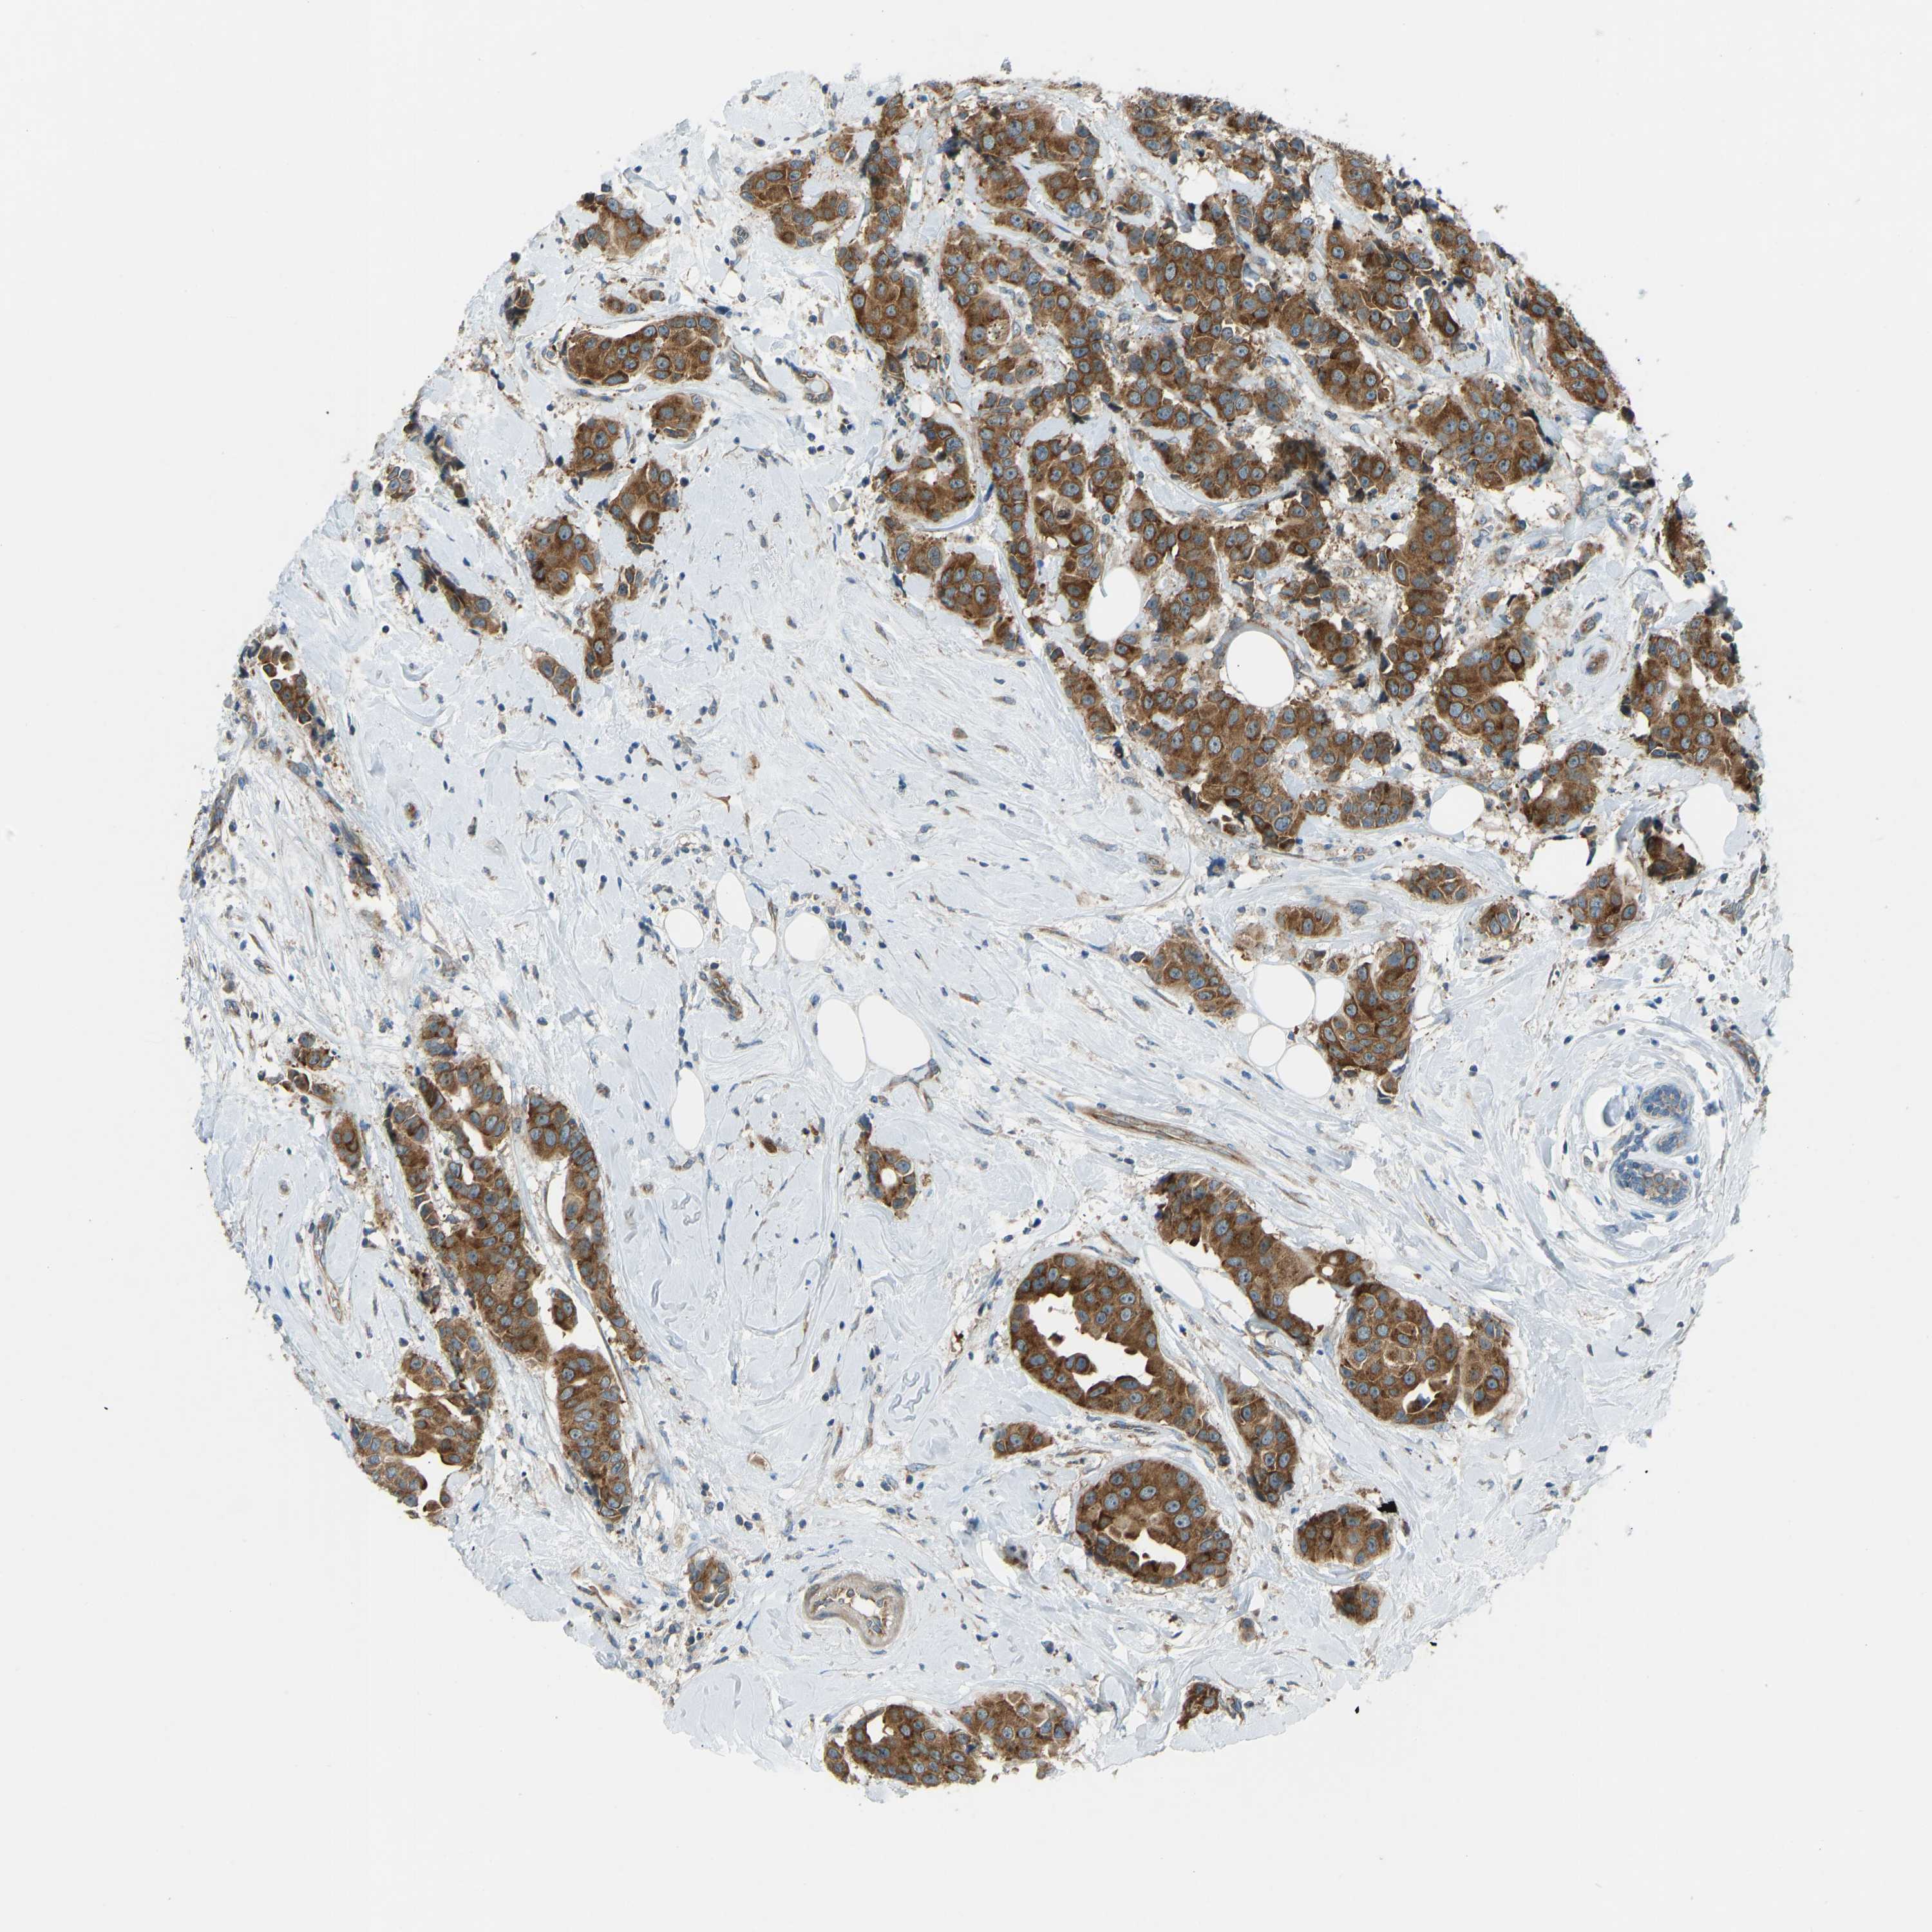

CANCER BREAST CANCER Show tissue menu

BRCA TCGA BRCA VALIDATION PROTEIN EXPRESSION